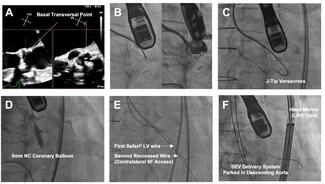

Brief Communication

Clinical Image